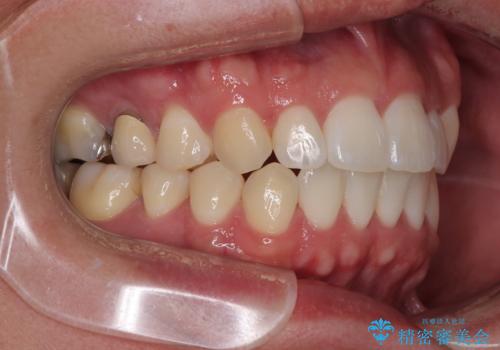

前歯のデコボコをささっと治す 短期間でのインビザライン矯正治療

- 前歯の反対咬合などを気にして来院された患者様です。

ワイヤー矯正、マウスピース矯正どちらでも対応可能であったので、ご本人の希望によりインビザラインにて矯正治療を行うこととしました。

毎日の装着時間をしっかりと守ってくださり、1年強の短期間で、あっという間に治療を終えることができました。